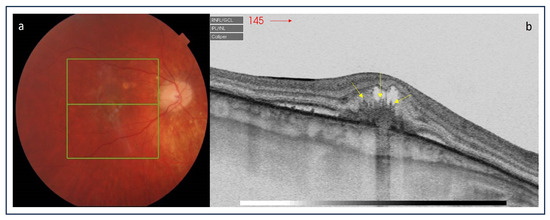

- Hoang, Q.V.; Cunningham, E.T., Jr.; Sorenson, J.A.; Freund, K.B. The “pitchfork sign” a distinctive optical coherence tomography finding in inflammatory choroidal neovascularization. Retina 2013, 33, 1049–1055. [Google Scholar] [CrossRef] [PubMed]

- Christakopoulos, C.; Munch, I. The ‘pitchfork sign’ on optical coherence tomography in a case of acute syphilitic posterior placoid chorioretinitis. Acta Ophthalmol. 2019, 97, e942–e943. [Google Scholar] [CrossRef]

- Rajabian, F.; Arrigo, A.; Grazioli, A.; Sperti, A.; Bandello, F.; Battaglia Parodi, M. Focal choroidal excavation and pitchfork sign in choroidal neovascularization associated with choroidal osteoma. Eur. J. Ophthalmol. 2021, 31, NP67–NP70. [Google Scholar] [CrossRef]

- Berensztejn, P.; Brasil, O.F. Re: The ’pitchfork sign’ a distinctive optical coherence tomography finding in inflammatory choroidal neovascularization. Retina 2015, 35, e23–e24. [Google Scholar]

- Falavarjani, K.G.; Au, A.; Anvari, P.; Molaei, S.; Ghasemizadeh, S.; Verma, A.; Tsui, I.; Sadda, S.; Sarraf, D. En face OCT of Type 2 neovascularization: A reappraisal of the pitchfork sign. Ophthalmic Surg. Lasers Imaging Retin. 2019, 50, 719–725. [Google Scholar] [CrossRef]